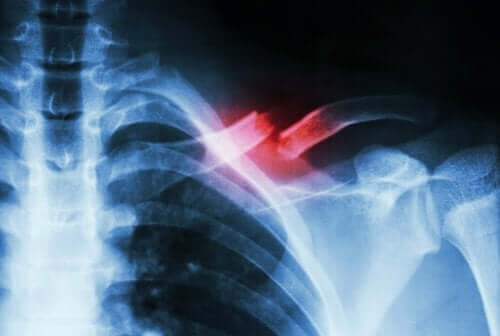

Et tretthetsbrudd, eller en stressfraktur som det også kalles, er når det er et lite brudd i et bein som er forårsaket av noe annet enn et hardt slag. Vanligvis er de forårsaket av gjentakende bevegelser eller av en rask økning av eller intensitet i aktiviteter.

Denne typen brudd er ikke så enkle å diagnostisere. Dette er grunnen til at det kreves både spesialister innen medisin og komplementære tester for å skille dem fra andre tilstander. Dette er fordi man vanligvis ikke oppdager bruddet ved å ta et røntgenbilde.